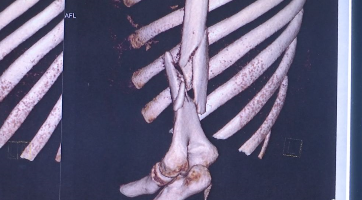

“拍了片子以后大家都大吃一惊,整个肱骨粉碎性骨折!”武进人民医院骨科主任历晓龙介绍。

通过X片可以看出,许同学骨折极其明显,骨头断为两截。